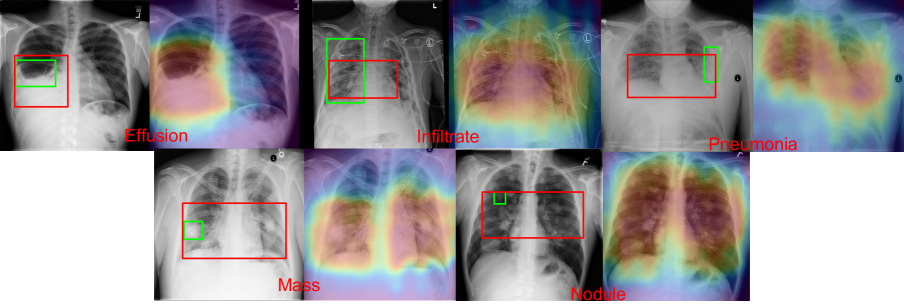

Refer to caption

Figure 6: This shows 5 ambiguous cases on 5 diseases where bounding annotations are bias. The input image is shown on the right, with two bounding boxes labels: green is the provided ground truth and red is our localized bounding boxes. The class-pooling output heatmap is shown on the right. The red bounding boxes are generated by applying a naive thresholding.

We presents 5 ambiguous cases on 5 diseases in Figure 6, which represents bias in localization annotations that leads to lower IoU score. In the case of ”Effusion”, the annotation outlined the liquid-lung boundary. Instead, our network includes the full liquid rinsed area. In the cases of ”Infiltration” and ”Pneumonia” that spread both lungs, the ground truth annotations only includes single lung, whereas our network captures both lungs. For cases like ”Mass” and ”Nodule”, the ground truth bounding box only highlights one of many instances of ”Mass” and ”Nodule”, but our localization highlights all instances.